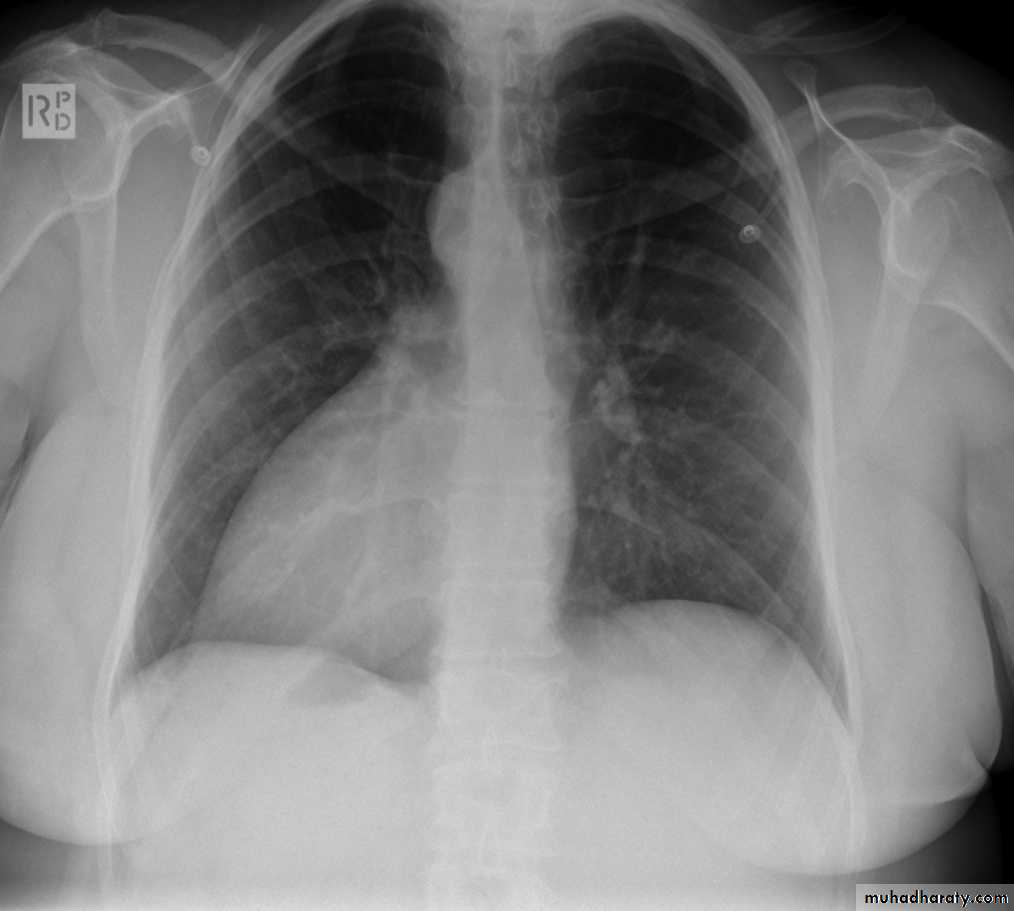

Pleural effusion

50.pleural effusion

51.pleural effusion .